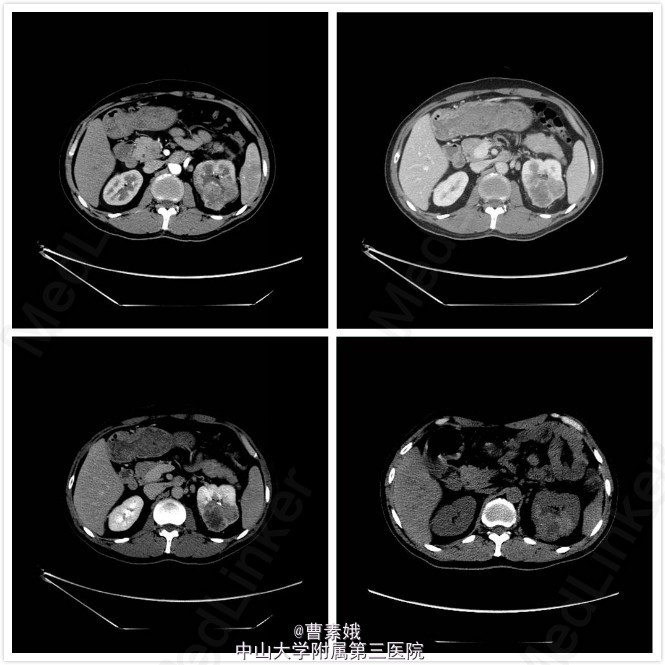

初步诊断:右股骨近端骨肿瘤(?)。 考虑右股骨肿物性质未明,遂于我院行全身PET/CT及腹部CT增强扫面,检查结果提示:1、左肾肿块并左肾静脉充盈缺损,代谢活跃,考虑左肾癌(透明细胞癌可能)并左肾静脉癌栓形成;双侧肾上腺座椅;腹膜后淋巴结转移;左侧股骨 经济股骨上段骨转移。随后患者行“左股骨肿物+左肾肿物穿刺活检术”,冰冻病理结果提示:左肾透明细胞癌,左股骨肿物考虑肾透明细胞癌转移。考虑患者肾透明细胞癌多发转移,无手术指征,转入肿瘤内科予索坦靶向治疗。